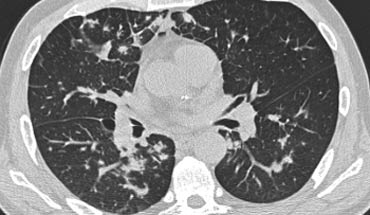

Hãy cuộn qua các hình ảnh bên trái.

Có nhiều vùng đông đặc.

Các dấu hiệu kèm theo bao gồm hạch to rốn phổi và trung thất.

Chẩn đoán phân biệt trên hình ảnh CT về cơ bản giống như trên X-quang ngực.

Kết quả mô bệnh học xác nhận sarcoidosis phế nang.

Chỉ có một gợi ý duy nhất cho chẩn đoán, đó là sự hiện diện của các nốt nhỏ có thể nhận thấy ở hình 3, nhưng rất khó quan sát.

Trường hợp này minh họa rõ ràng rằng sarcoidosis thực sự là “kẻ bắt chước vĩ đại”.